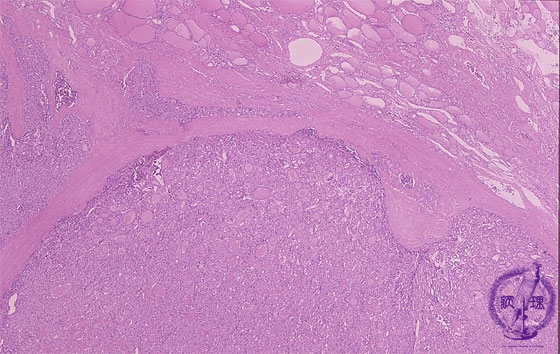

- (9)Follicular carcinoma of the thyroid

Microscopic findings (HE stain, low power view). Thyroid tumor with fibrous capsule. The presence of a tumor nest (arrows) outside the capsule is suggestive of capsular invasion.